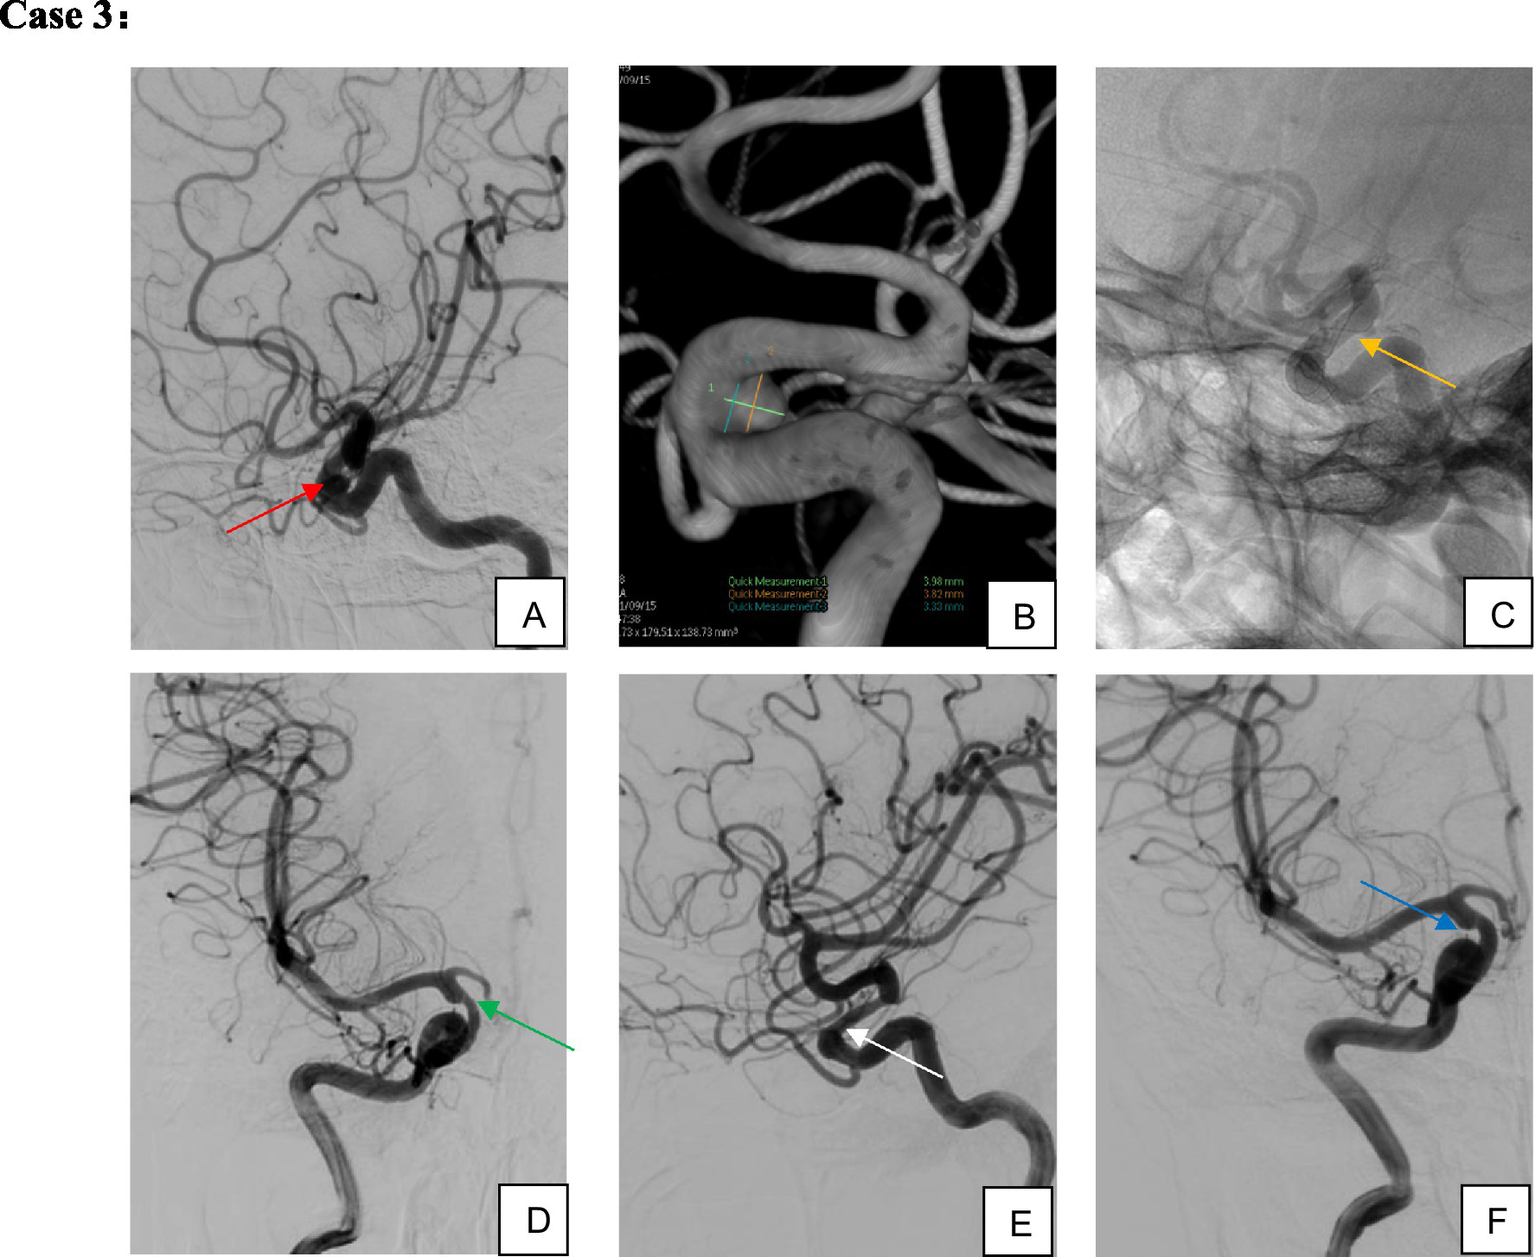

Figure 4

Female, 67 years old, aneurysm of the ophthalmic segment of the right internal carotid artery. (A,B) Right internal carotid artery ophthalmic segment wide-necked small aneurysm; (C) single TFD implantation; (D,E) four-month postoperative imaging demonstrated complete aneurysm occlusion and moderate in-stent stenosis; (F) without specific intervention, the in-stent stenosis spontaneously resolved on 10-month follow-up imaging while the patient remained on single-aspirin therapy.